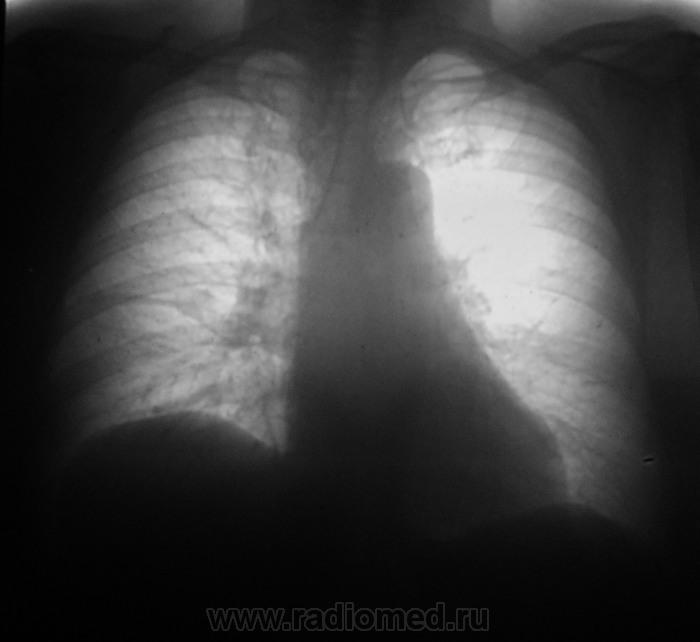

Здравствуйте!выпот по добавочной щели справа?уменьшение нижней доли справа?доснять правый бок

Возможна гиповентиляция правого легкого

Верхушка справа не красивая. И какая то тяжистость в н/доле.

Справа прозрачность снижена, и правый купол диафрагмы слишком высоко, присоединяюсь к мнениям о гиповентиляции

Добавил бы к вышеизложенному следующее:

1. Впечатление "закаканности" правой верхушки.

2. Около горизонтальной щели справа толи фокус, толи инфильтрация.

3. Обратил бы внимание на левое легкое. Возможна вторая ст. нарушения бронхиальной проходимости (гипервентиляция).

присоединяюсь к вышеизложенному,+слева в костодиафрагмальном синусе уплотнена плевра(или издержки снимка?), немного смущает *пуговица *аорты

Что-то похожее на инфильтрацию в верхушке справа - томография.

Там же дисковидный ателетаз.

Интересный ход добавочной щели.

На мой взгляд. легочный рисунок усилен, корни расширены. Мнение о саркоидозе, пневмокониозе.